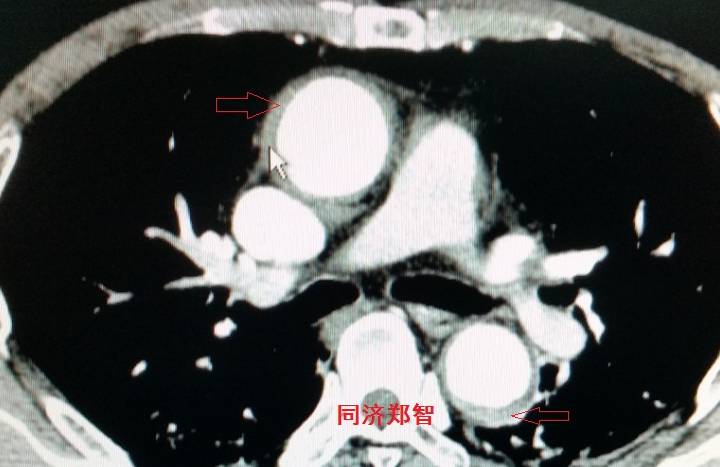

病例七

平扫CT提示升主动脉及降主动脉内膜片,CTA证实为A型主动脉壁间血肿。